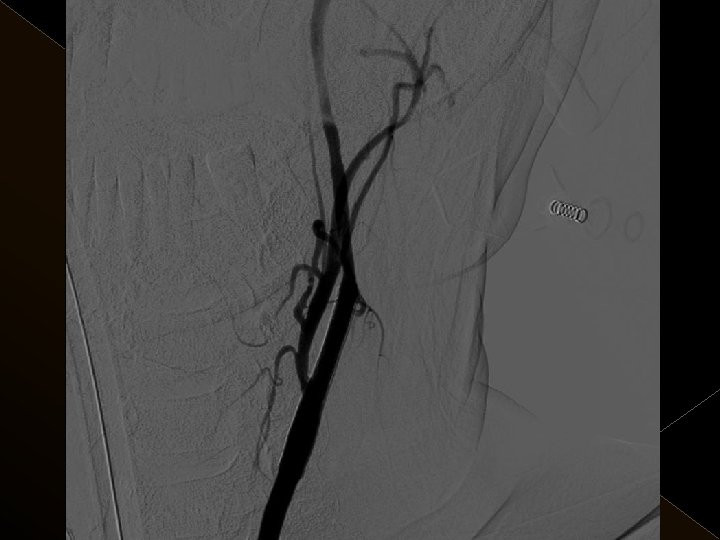

� 25 hasta (16 K, 9 E) , 27 vaskuler okluzyon � 16 orta serebral arter (MCA), � 6 baziler arter ve � 5 internal karotis arter (İCA) düzeyinde olmak üzere � Toplam 25 hasta, 27 tıkanıklığa (6 sı hariç) iv tpa sonrası endovaskuler yolla müdahale edildi

� İnme tedavisinde iv tpa uygulamasını takiben � intraarteriyel (İA) trombolitik tedavi (ia tpa ve ia mekanik trombolizis) � İA stent yardımı ile trombektomi yöntemleri kullanılarak tedaviye cevap ve komplikasyonlar araştırıldı.

KOMPLİKASYONLAR Ponksiyon bölgesi komplikasyonları � Trombektomi stentine ait komplikasyon (*1) � Diseksiyon(*2) � Karotikokavernöz fistül (‘ 1) � Hemorajik komplikasyonlar(‘ 5) Semptomatik-nonsemptomatik � İskemik komplikasyonlar (3) � Reoklüzyon (2 i. a) � Kontrast madde nefropatisi �